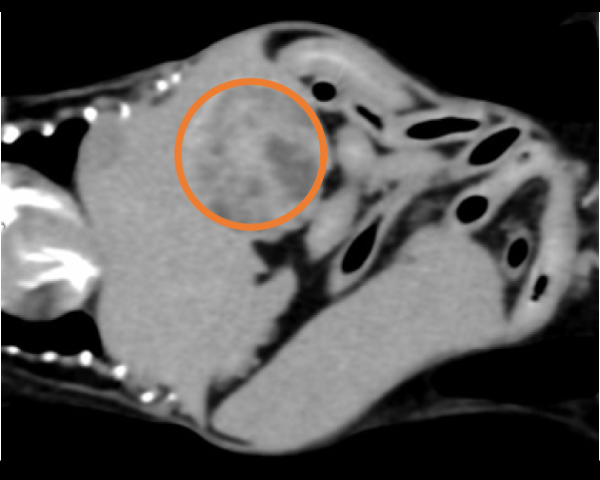

造影CT検査にて腫瘤の浸潤・転移を評価

脾臓の多発性吸収結節像を確認